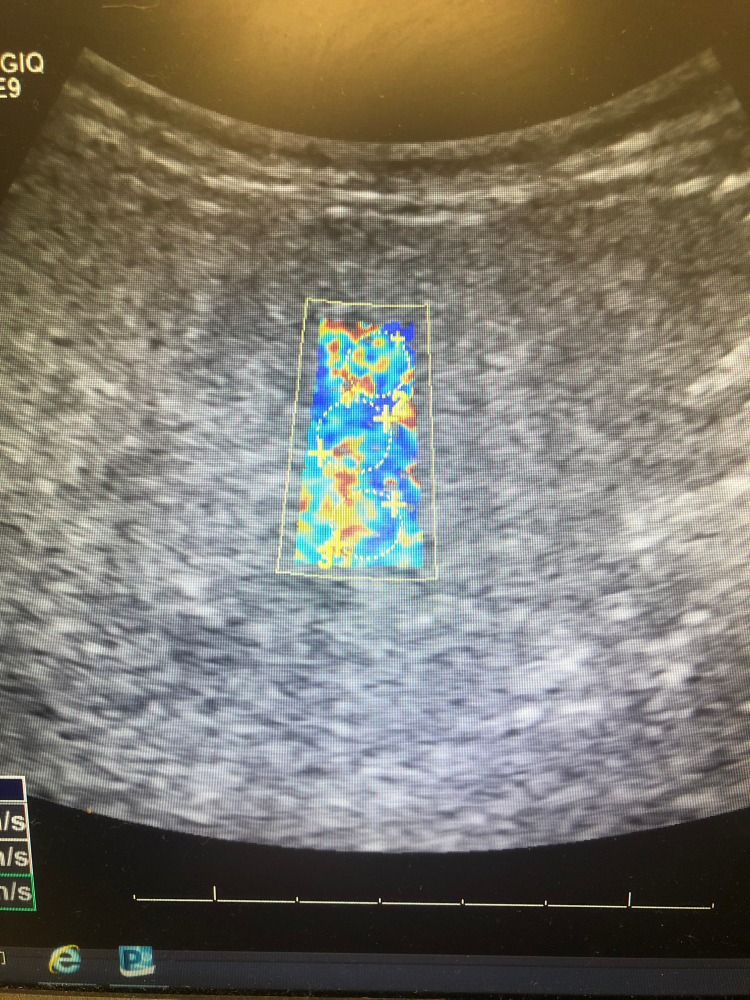

Included are images of elastography taken of our patient’s liver, courtesy of Vicente Hernandez from the Jackson Memorial Hospital Ultrasound Department. Twelve regions are selected from a patient’s liver to calculate a mean velocity of transmission, indicating the degree of elasticity, which correlates with underlying tissue fibrosis. Figure 1 shows an image of our patient’s liver, which displays significant areas of heterogeneous yellow and red intermixed with blue, the former of which correspond with areas of increasing elasticity.

Figure 1. Elastography of Patient's Liver.

The first three of twelve separate sections of our patient's liver examined using elastography. Note heterogenous blue, green, yellow, orange, and red admixed, indicating increasing areas of fibrosis.